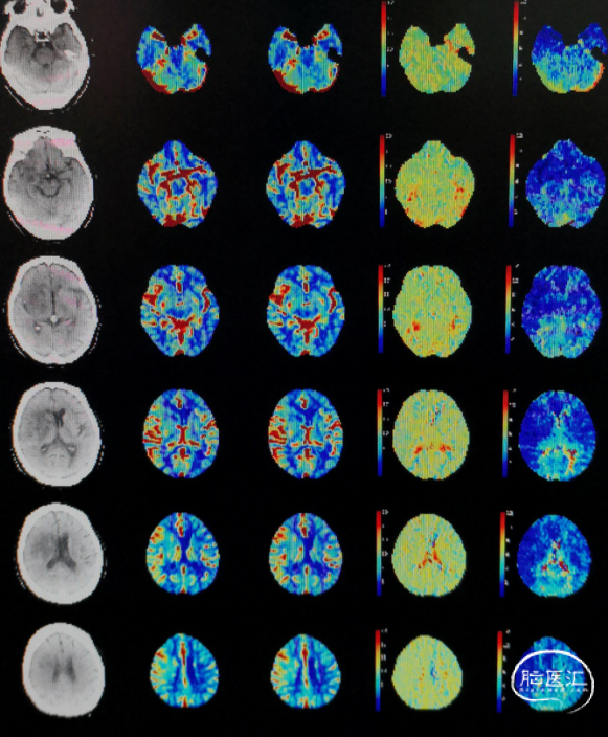

脑CT灌注:右侧额叶、颞叶、顶叶缺血低灌注;mismatch 155ml。

术后第5天复查脑CT灌注:相对于左侧,右侧半球高灌注